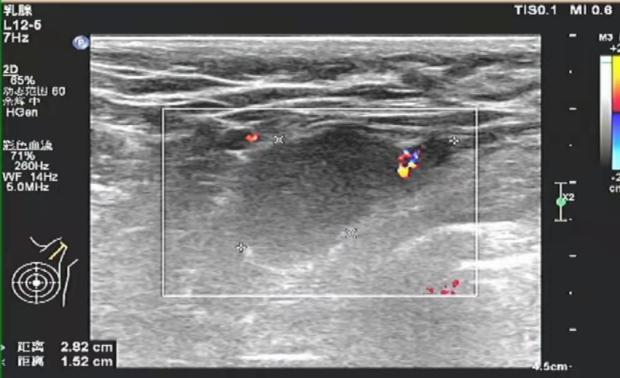

2021-11 乳腺超声:左乳内上象限11点钟至外下象限4点钟方向乳头中央区深面可见一个异常回声区,与导管关系密切,局部延伸至乳头中央区深面,范围约10.5×1.8cm,距皮4mm,形状呈不规则形,边界不清,肿块内部可见丰富紊乱的血流信号。左侧腋窝可见3-4个异常实质回声,大小不等,最大约2.7×1.5cm,形状呈不规则,边界欠清楚。

图1. 新辅助治疗前乳腺超声